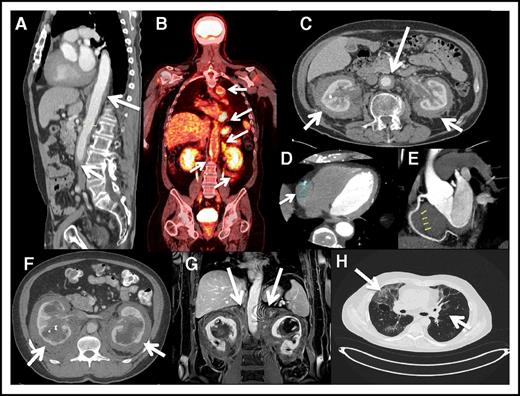

Coated aorta or circumferential encasement of the aorta (Figure 2A-C) was apparent in 62% of patients. The most common cardiac manifestation was pseudotumor of the right atrioventricular groove, apparent on cardiac CT (Figure 2D-E) in 37% of patients. Rarely involved vessels included the portocaval system, causing portal hypertension in 1 case and mesenteric vessel disease producing bowel ischemia in 3 cases. Stents were used to bypass the stenosis. A total of 5 patients had pericardial involvement; 2 had cardiac tamponade, and 4 needed pacemakers for abnormal rhythms. None of the cases had evidence of valvular disease or cardiac failure.

Cardiovascular, retroperitoneal, and lung images of ECD patients. (A) Sagittal reconstruction postcontrast CT demonstrates encasement of the thoracic aorta down to the bifurcation. (B) Coronal FDG PET-CT scan showing increased FDG uptake in the thoracic and abdominal aorta. Symmetrically encased kidneys “hairy kidney” showing increased FDG uptake. (C) Axial CT with contrast demonstrates mass-like enhancement encasing the kidneys symmetrically (“hairy kidney”). In addition, there is circumferential encasement and narrowing of the abdominal aorta (arrow). (D) Cardiac CT showing partial encasement of the right coronary artery. (E) Cardiac CT showing partial encasement of the right coronary artery. (F) Axial postcontrast CT image of the upper abdomen demonstrating mass-like perinephric stranding surrounding the kidneys with bilateral hydronephrosis. Hyperdense material within the right collecting system is a ureteral stent. (G) Postcontrast coronal MRI image of the kidneys demonstrating extension of the perinephric mass into the adrenal bed and encasement of the adrenals (arrows). (H) High-resolution CT of the chest showing interstitial fibrosis.

Retroperitoneal involvement

One-third of patients had a history of renal impairment prior to their NIH visit. A total of 65% of patients (39 out of 60) exhibited encasement of the kidneys and involvement of the retroperitoneal space (Figure 2F-G), causing renal artery stenosis in 54% of cases (21 out of 39) and ureteropelvic junction obstruction in 51% of that group of patients (20 out of 39); 13 cases were affected by both renal artery stenosis and ureteropelvic junction obstruction. Hypertension controlled by renal artery stents was reported in 4 cases and hydronephrosis needing ureteral stents in 6. Three patients had a history of requiring nephrostomy tubes. In these cases, renal function was impaired, but neither renal transplantation nor dialysis was under consideration.

Patients were generally asymptomatic from pulmonary disease, but some experienced dyspnea with exertion. Interstitial fibrosis with reticular pattern was apparent on high-resolution chest CT (Figure 2H) in 52% of patients; plain films of the chest did not reveal lung disease. Pulmonary function tests showed a restrictive pattern in 30% and an obstructive pattern in 7% of patients. The mean diffusing capacity of the lungs for carbon monoxide level was 23.0 mL/mm Hg per minute, with a range of 8.5 to 36.